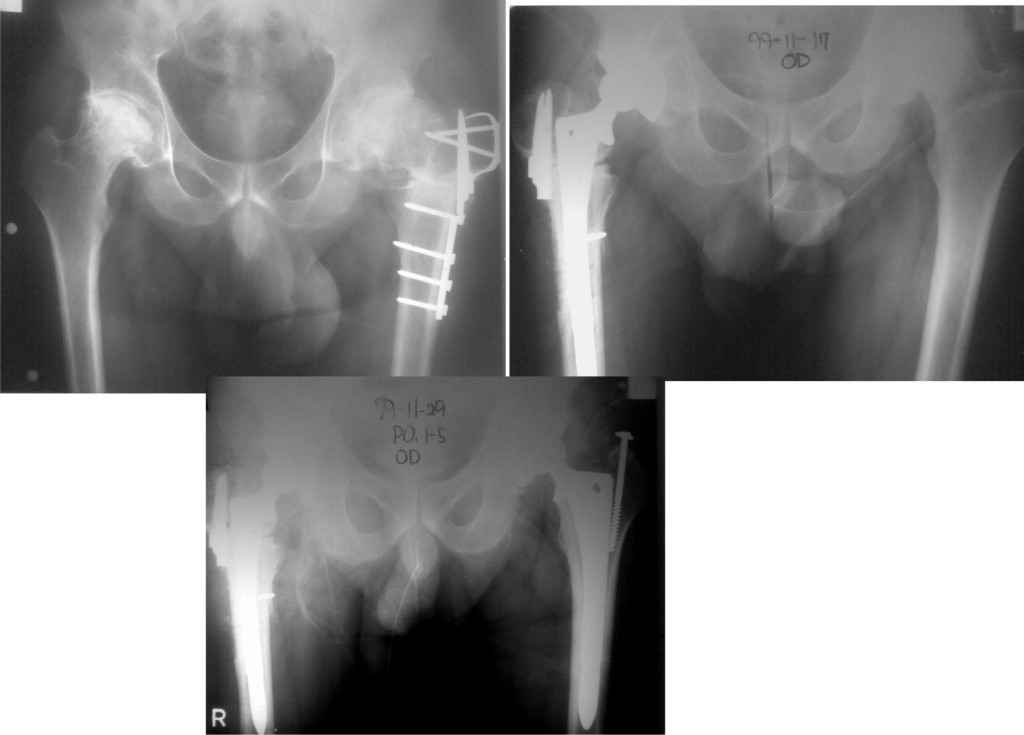

У меня опыт по эндопротезированию совсем небольшой. Еще 5 лет тому назад у нас в городе не было протезирования. Во вложении снимки одного больного из нашего города. который оперировался в 1999 году в Южной Корее. разница по времени замены второго сустава 11 дней. Больной по настоящее время ходит без проблем, особых жалоб не предъявляет, весит он 98 кг. Может быть есть смысл подождать, по наблюдать а оперировать никогда не поздно.